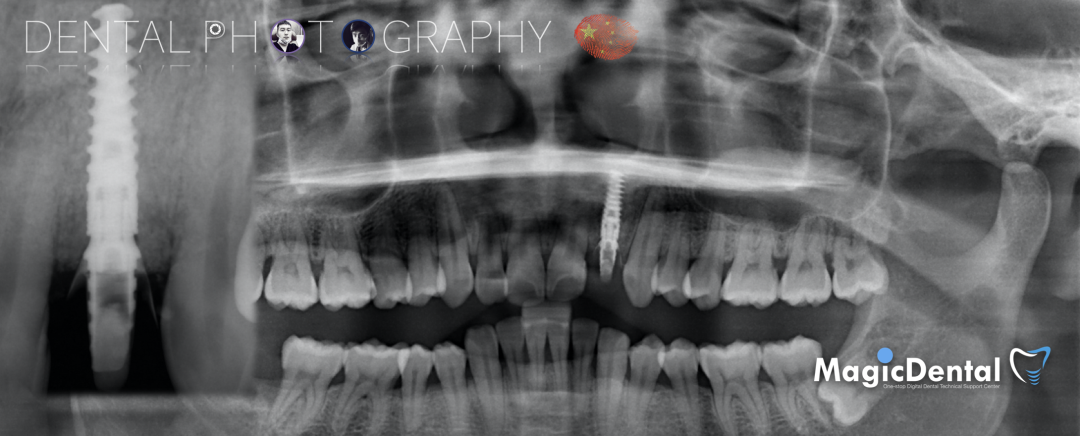

术前CBCT

22缺失,且牙槽骨唇颚侧宽度较窄,38,48近中阻生。

治疗计划:水平骨增量,拔除四区近中阻生智齿,下颌升支外斜线处取块状骨,移植骨块至受区(22唇侧),种植修复22缺失牙。